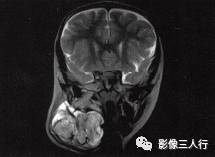

女性,4岁。右侧颈部包块。

颈部淋巴管瘤

A.B.MRI T1WI显示右侧上颈部大片混杂低信号,其内见蜂窝状更低信号,肌间隙显示不清,并见点、线状高信号。咽、喉、气管受压移位;C〜F.T2WI的横断面、冠状面病变表现为不均匀高信号,形态不规则,可见病变向上、下,向左、右延伸,有“见缝就钻”的特点,气管及周围软组织受压移位

颈部淋巴管瘤(术后病理)。

2.T1WI显示右侧颈部大片混杂低信号,其内见到多个类圆形囊性低信号。

3.T2WI病变表现为不均匀的高信号,形态不规则,其内可见分隔,具有“见缝就钻”的特点。气管及周围软组织受压移位。